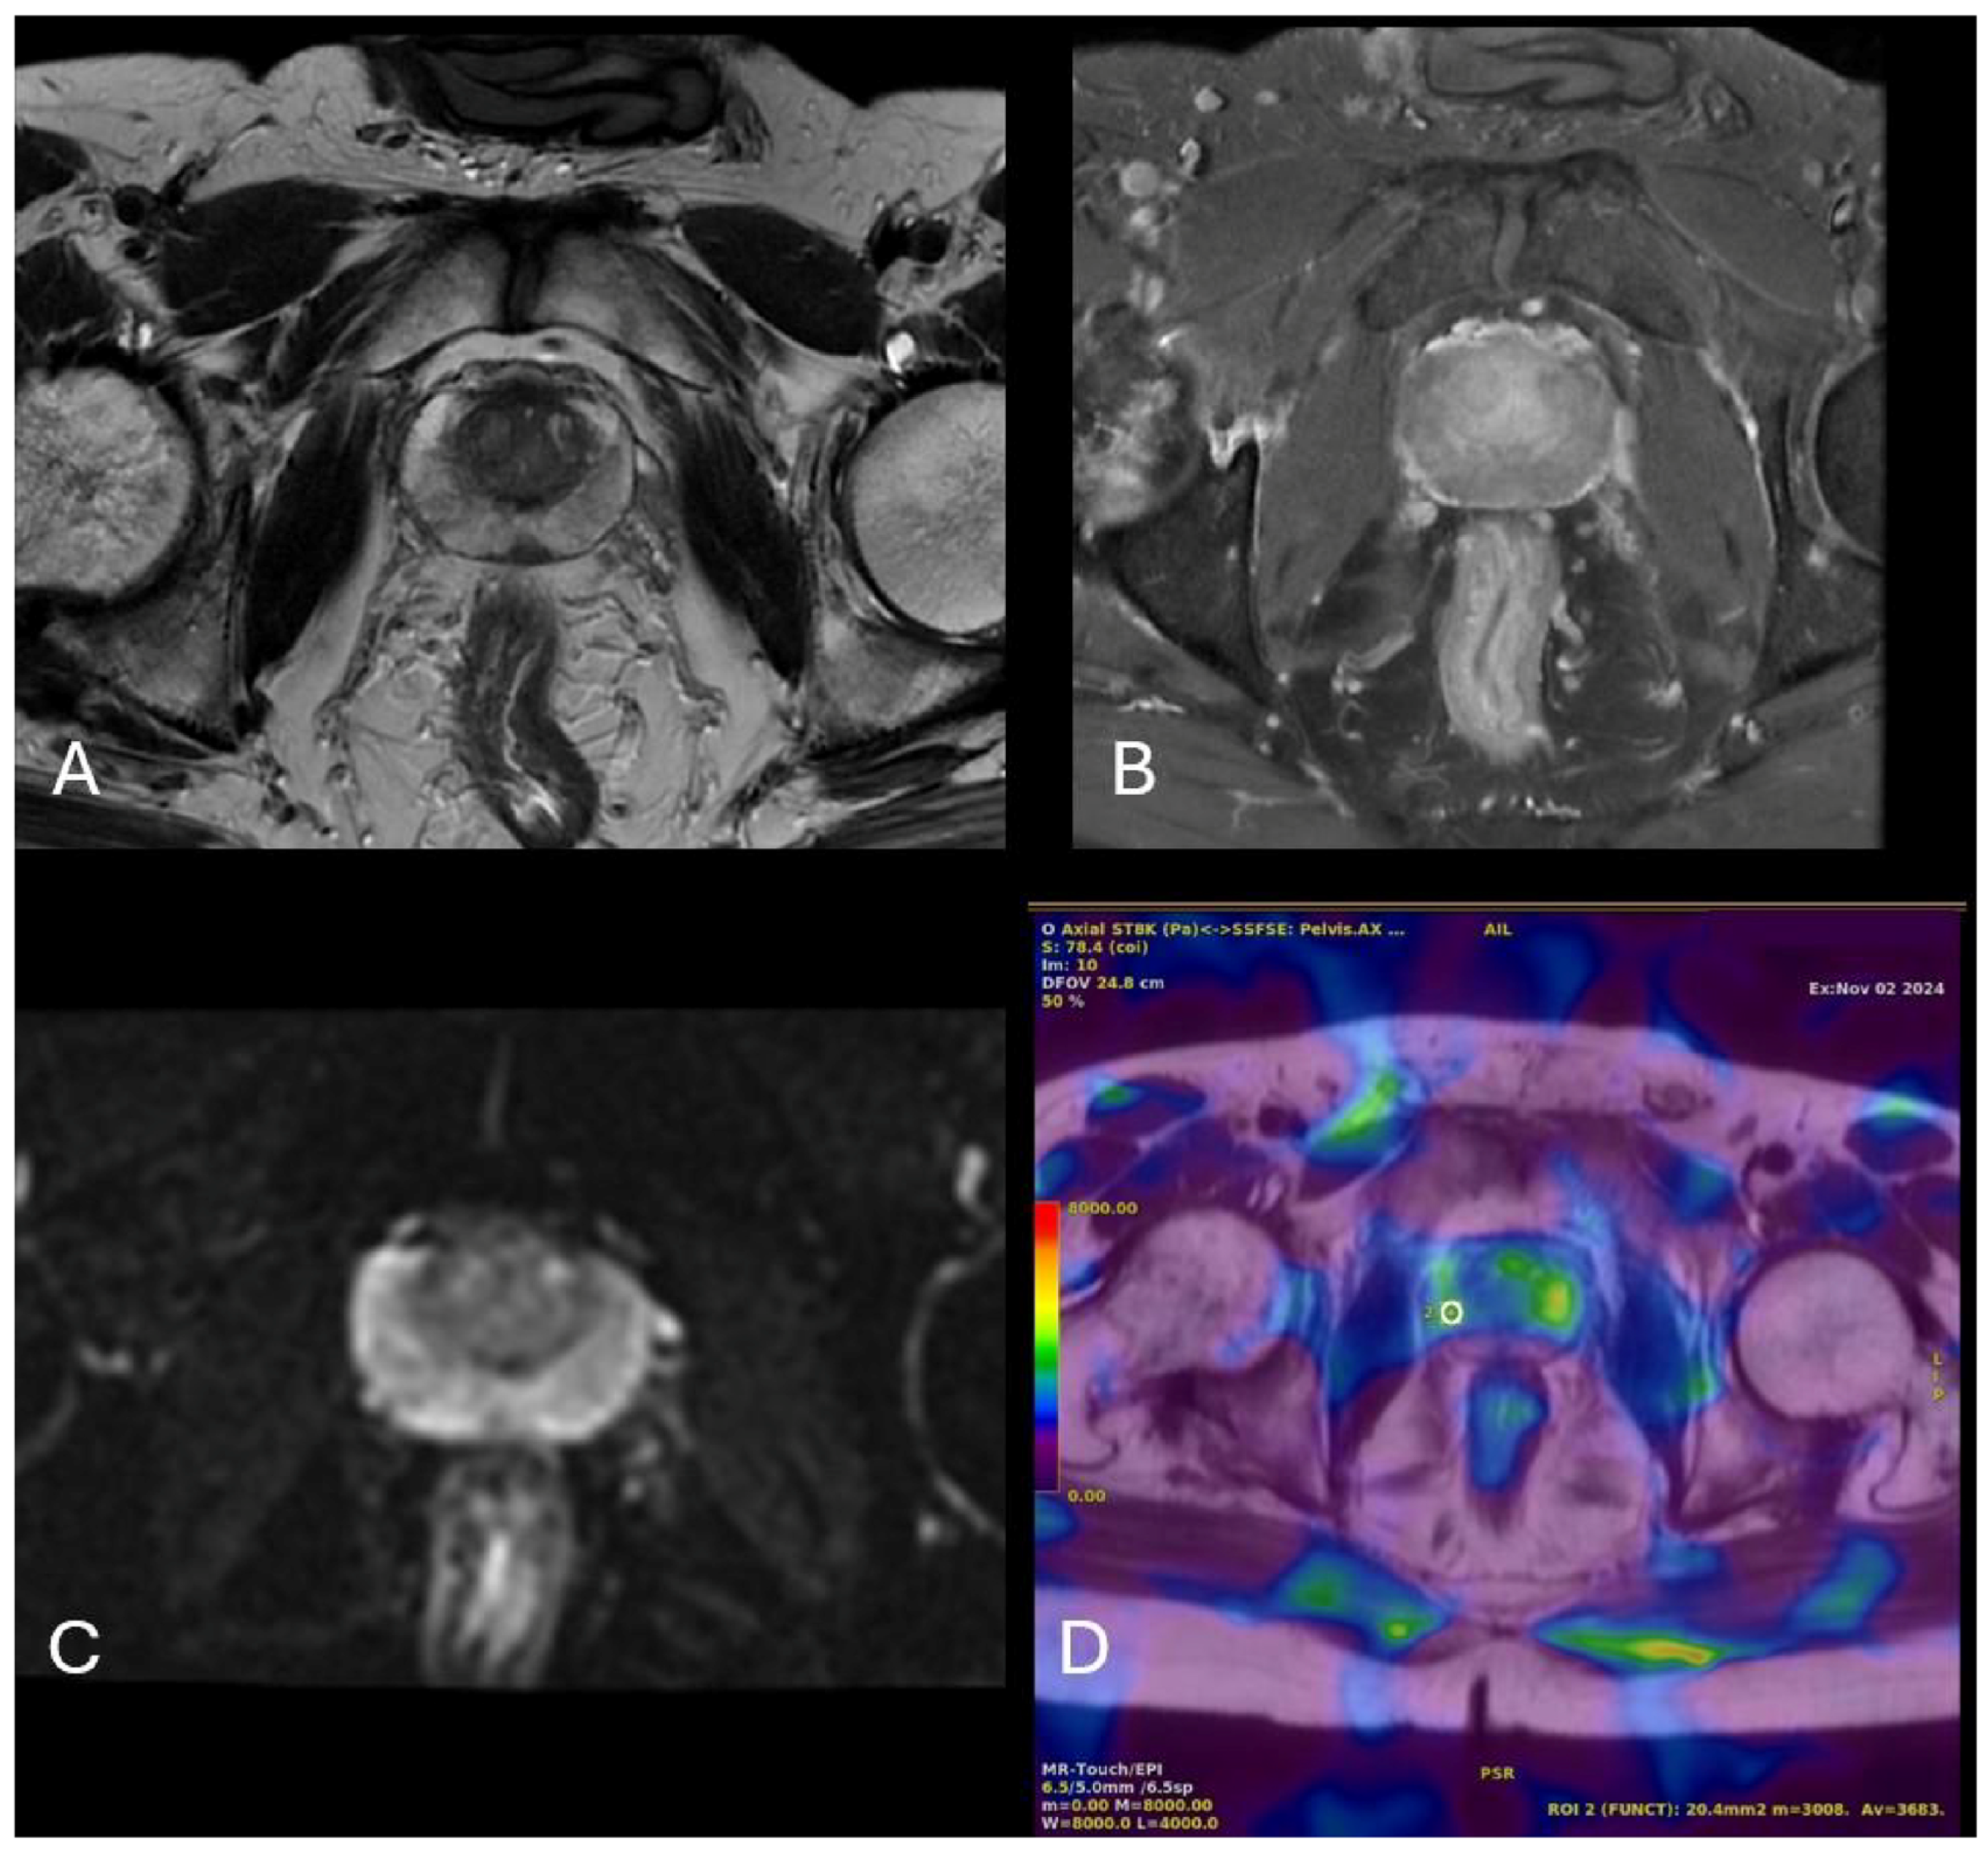

2.4. Radiological Measurements